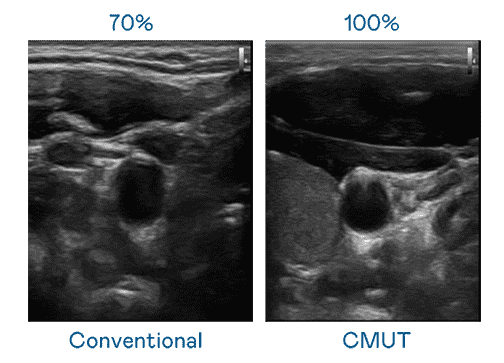

CMUT 技术是一种用电容式微机电元件来产生超音波讯号的技术。。。。与传统 PZT 压电式技术相比,,,,CMUT 频宽增加 30%,,更宽频的超音波讯号让影像解析度大幅提升,,,是实现高影像品质医疗超音波扫描、、、、促进精准医疗发展的关键技术。。

大频宽带来超清晰影像

超音波影像的解析度高低,,,,首先取决于探头能发出的讯号频宽。。。。财神娱乐 CMUT 可提供高清晰的超音波讯号,,提供高频宽、、、高灵敏度、、影像纹理细节更高的超音波影像,,,协助医护人员缩短影像判读时间及利用精准的医疗影像进行诊断。。。